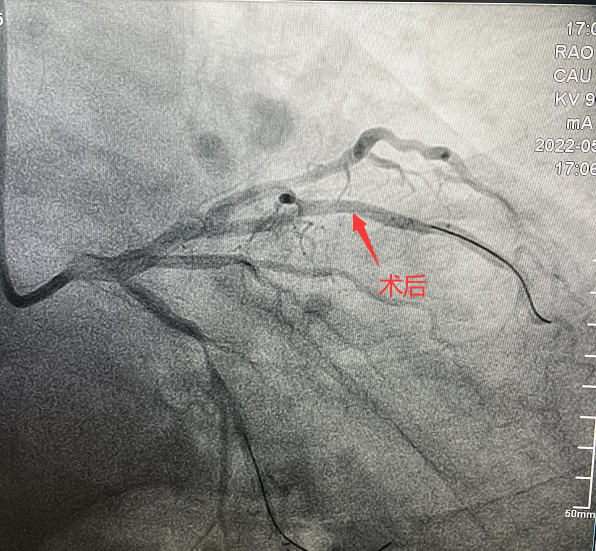

患者,51歲,男性,入院診斷為:冠心病、不穩定型心絞痛。冠狀動脈造影顯示對角支90%狹窄病變。對于該類患者,通過介入治療(PCI)方式早期干預相關血管可明顯減輕患者癥狀,減少死亡率、并發癥,改善患者的預后。在醫生與患者及家屬溝通時,患者家屬提到,他們了解得知臨床有一種新型的可吸收支架,置入體內后能完全被降解和吸收,患者及家屬希望能用這種新型的支架進行手術治療。由于生物可吸收支架有著嚴格的適應癥,因此經過嚴格評估,最終對患者進行了Xinsorb生物可吸收支架(BRS)置入術。支架植入術后,經IVUS檢查,支架貼壁良好,結果完美,手術順利結束。

手術造影圖